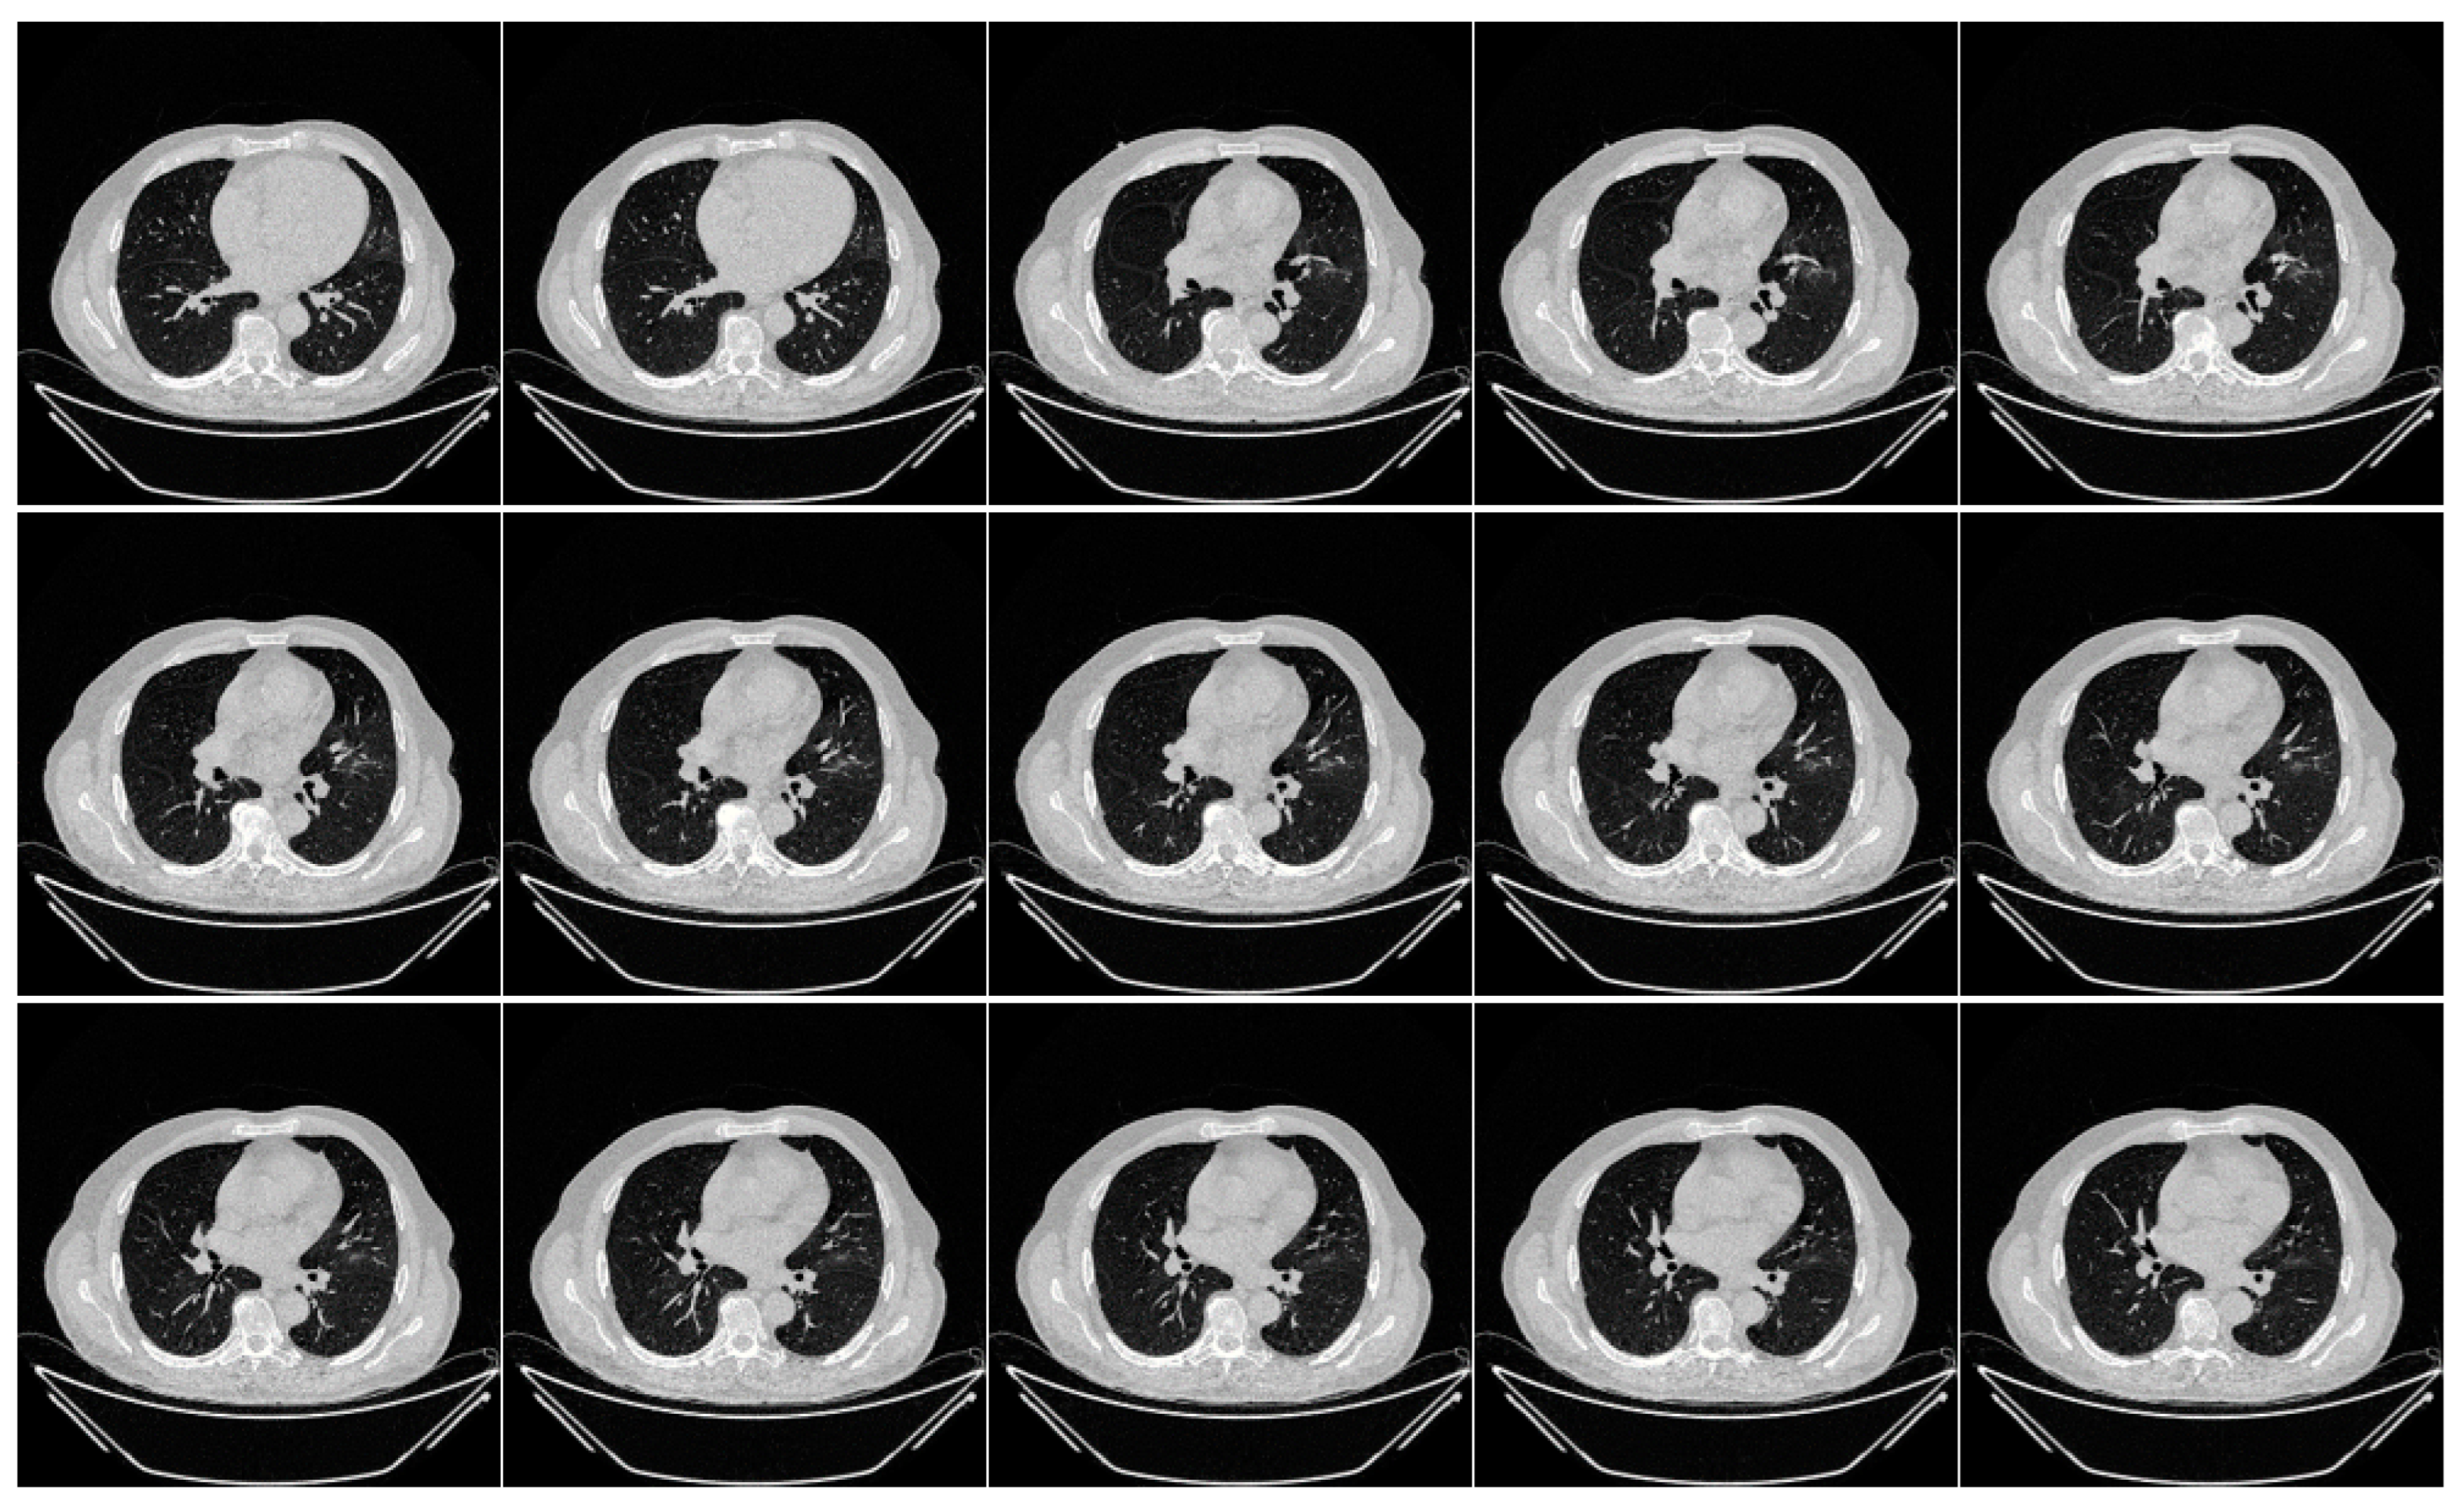

Appendix A

Appendix A includes three figures: Figure A1, Figure A2 and Figure A3. These diagrams are sample images of the dataset. Figure A1 is CroMED (COVID), Figure A2 depicts NovMED (COVID), and Figure A3 shows NovMED (Control).

Figure A2.

Raw “Control CT slices” taken from NovMED Dataset.

Figure A3.

Raw “COVID-19 CT slices” taken from NovMED dataset.